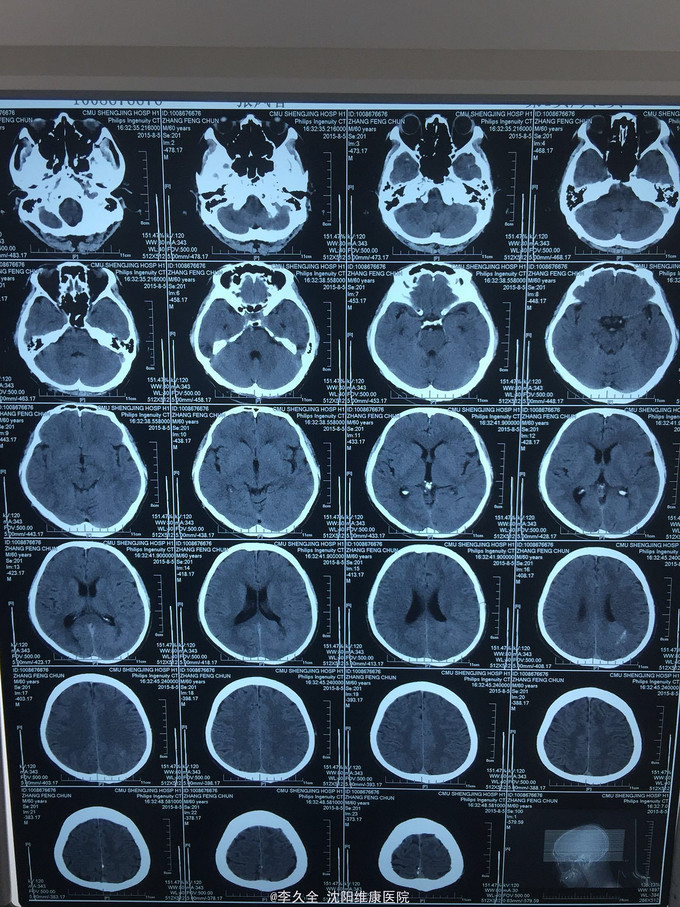

男,62岁,以头晕、视野缺损、记忆力减退、失写、失算7个月入院! 现病史:去年7月出现头晕,就诊于医院,行头CT:代诉未见异常,口服药物无效,后出现右侧视野缺损,走路撞墙、撞门,就诊于当地医院、北京协和医院,考虑“㬵质瘤”,近3个月出现近事遗忘为主,平时写字不会,计算力下降,不认识人! 既往史:2型糖尿病5年!

查体:BP:150/80mmHg,心肺腹无异常。神清,不能言语,失写、失算、失认,双曈孔等大正圆,直径3.0mm,光敏,四肢能够活动,右侧肌张力增高,巴氏征R+L-,颈强3横指,克氏征阳性! 影像MR:

1.颅内占位,胶母可能大! 2.2型糖尿病